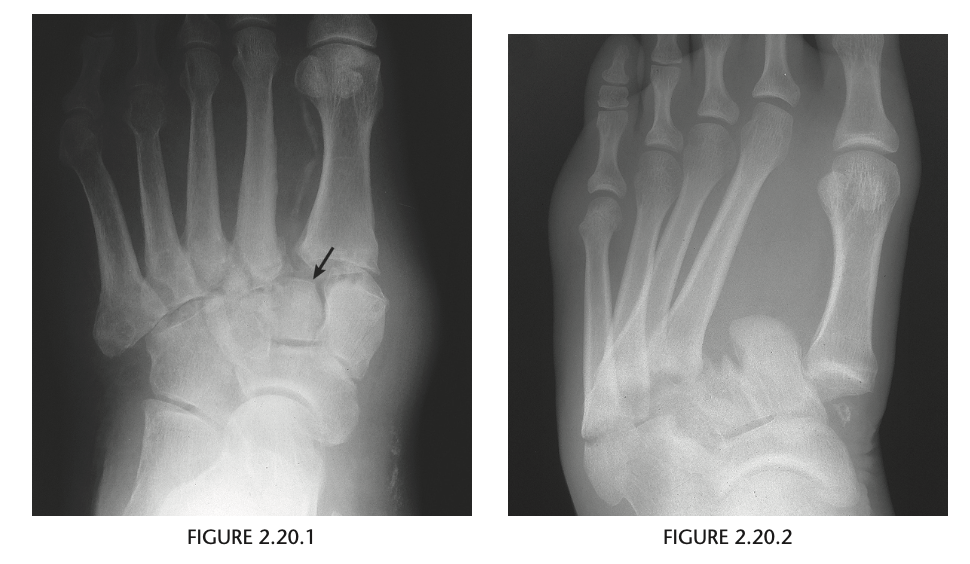

A 65-year-old woman with insulin-dependent diabetes and recent swelling of the left foot

Anteroposterior view of the left foot

(Fig. 2.20.1) demonstrates vascular calcification,

soft-tissue swelling, lateral subluxation of the sec-

ond through the fifth metatarsals in relation to the

cuneiforms, and early destructive changes at the

tarsal-metatarsal joints. Notice the disruption of

the normal parallel alignment of the medial aspect

of the second cuneiform with the medial aspect of

the second metatarsal base (arrow).

Lisfranc fracture-dislocation, homolat-

eral type

On imaging, the Lisfranc

fracture-dislocation is seen as dorsal and lateral dis-

location of the metatarsal bases in relation to the cu-

neiforms. It is the most common dislocation in the

foot.

There are two distinct forms of the Lisfranc

fracture-dislocation: homolateral and divergent. In

the homolateral type, all metatarsals are dislocated

laterally in relation to the cuneiforms.

In the divergent type, there is lateral displacement of

the second through the fifth metatarsals and medial

or dorsal shift of the first metatarsal.

The characteristic radio-

graphic changes include soft-tissue swelling, vascular

calcification, bone destruction and fragmentation,

multiple fractures, and soft-tissue ossific debris from

the destructive changes

MR imaging can be useful in detecting bone marrow

edema, subcutaneous abscess, and sinus tracts